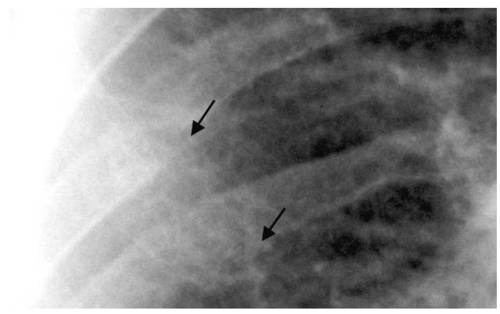

Перелом ребер. Самое распространенное повреждение грудной клетки. Переломы ребер составляют около 16% от общего числа переломов. У пожилых людей переломы ребер встречаются чаще, что обусловлено возрастным уменьшением эластичности костных структур грудной клетки. Переломы ребер сопровождаются болью в груди и приводят к ограничению подвижности грудной клетки, по этой причине дыхание становиться более поверхностным, что может вызвать нарушение легочной вентиляции. Множественные переломы ребер могут сопровождаться повреждением органов грудной клетки и представлять опасность для жизни пациента. Диагноз перелома ребер выставляется на основании данных рентгенографии, при необходимости проводится УЗИ плевральной полости и ее пункция.

Причиной перелома ребер может стать падение, прямой удар в область ребер или сдавление грудной клетки. Чаще всего ребра ломаются в месте наибольшего изгиба - по боковым поверхностям грудной клетки. При переломе одного ребра отломки смещаются очень редко. Множественные переломы ребер часто сопровождаются смещением отломков (перелом со смещением). При этом отломки своими острыми концами могут повредить плевру, легкие и межреберные сосуды.